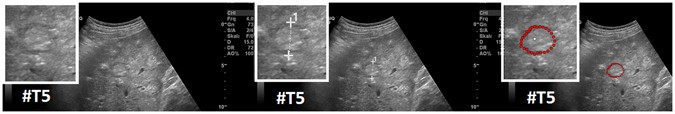

Segmentation results (manual/interactive) of a hyperechoic appearing metastasis with a hypoechoic halo (metastasis of a colon cancer), where the metastasis shows a very low contrast to the surrounding liver parenchyma. The native image with a zoomed view of the metastasis is presented in the left image. A manual measurement of the maximal metastasis diameter (white dotted line between two white crosses) is shown in the middle image. Finally, the rightmost image presents the interactive segmentation results (red dots) with the corresponding user-defined seed point (white). Note: figure adapted from26.

Figure 9 presents several screenshots from a video, where two metastases of a colon cancer35 in one image were segmented interactively (from the top to the bottom). The upper image presents the native acquisition. The next image presents the position of the mouse cursor where the user started the interactive segmentation. The third image presents the first segmentation result (red dots) at the position of the mouse cursor. In the following image, the user moved the seed point (white dot) for the segmentation slightly to the right to get a better segmentation. After being satisfied with the segmentation of the first metastasis, the user moved the seed point to the second metastasis on the right. As seen in the screenshots of the video, the resulting segmentation contours (red dots) collapsed, because, in this area, no lesion is present (note: the screenshots present only a fraction of the whole video). When the user reached the second metastasis on the right, the red segmentation contour automatically expanded again and adapted to the metastasis border (lower two images). The lower image presents the final outlining of the second metastasis, where the user stopped the interactive segmentation process. Moreover, Fig. 10 shows a side-by-side comparison of manual expert measurements (left) and interactive segmentation results (right) for the two liver metastases from Fig. 9.

Several screenshots from a video where two metastases of a colon cancer in one image were segmented interactively (from the top to the bottom). The upper image presents the native acquisition. The next image presents the position of the mouse cursor where the user started the interactive segmentation. The third image presents the first segmentation result (red dots) at the position of the mouse cursor. In the following image, the user moved the mouse and therefore the seed point (white dot) for the segmentation slightly to the right to get a better segmentation. After being satisfied with the segmentation of the first metastasis, the user moved the mouse to the second metastasis on the right. As seen in the screenshots of the video, the resulting segmentation contours (red dots) collapsed, because in this area, no metastasis is present (note: the screenshots present only a fraction of the whole video). When the user reached the second metastasis on the right, the red segmentation contour automatically expanded again and adapted to the metastasis border (lower two images). The lower image presents the final outlining of the second metastasis where the user stopped the interactive segmentation process.